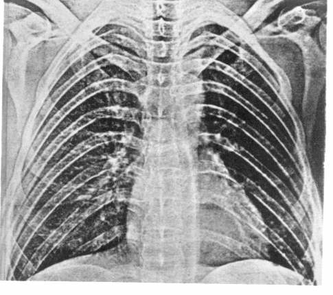

Для получения первой, наиболее общей, информации о характере рентгенологических изменений в легких и грудной полости (наряду с флюорографией) в некоторых клиниках стала использоваться электрорентгенография. Важнейшим достоинством метода электрорентгенографии являются его высокая экономическая эффективность, исключение расходов на оснащение специальных фотолабораторий и реактивов, необходимых для рентгенографии. Процесс электрорентгенографии не зависит от водоснабжения, получение крупноформатных снимков происходит на свету. Изображение воспроизводится на селеновой пластине и затем переносится на бумагу (рис. 2).

Электрорентгенография имеет неоспоримые преимущества при проведении неотложной рентгенологической диагностики.

Рис. 2. Электрорентгенограмма грудной клетки. Норма.